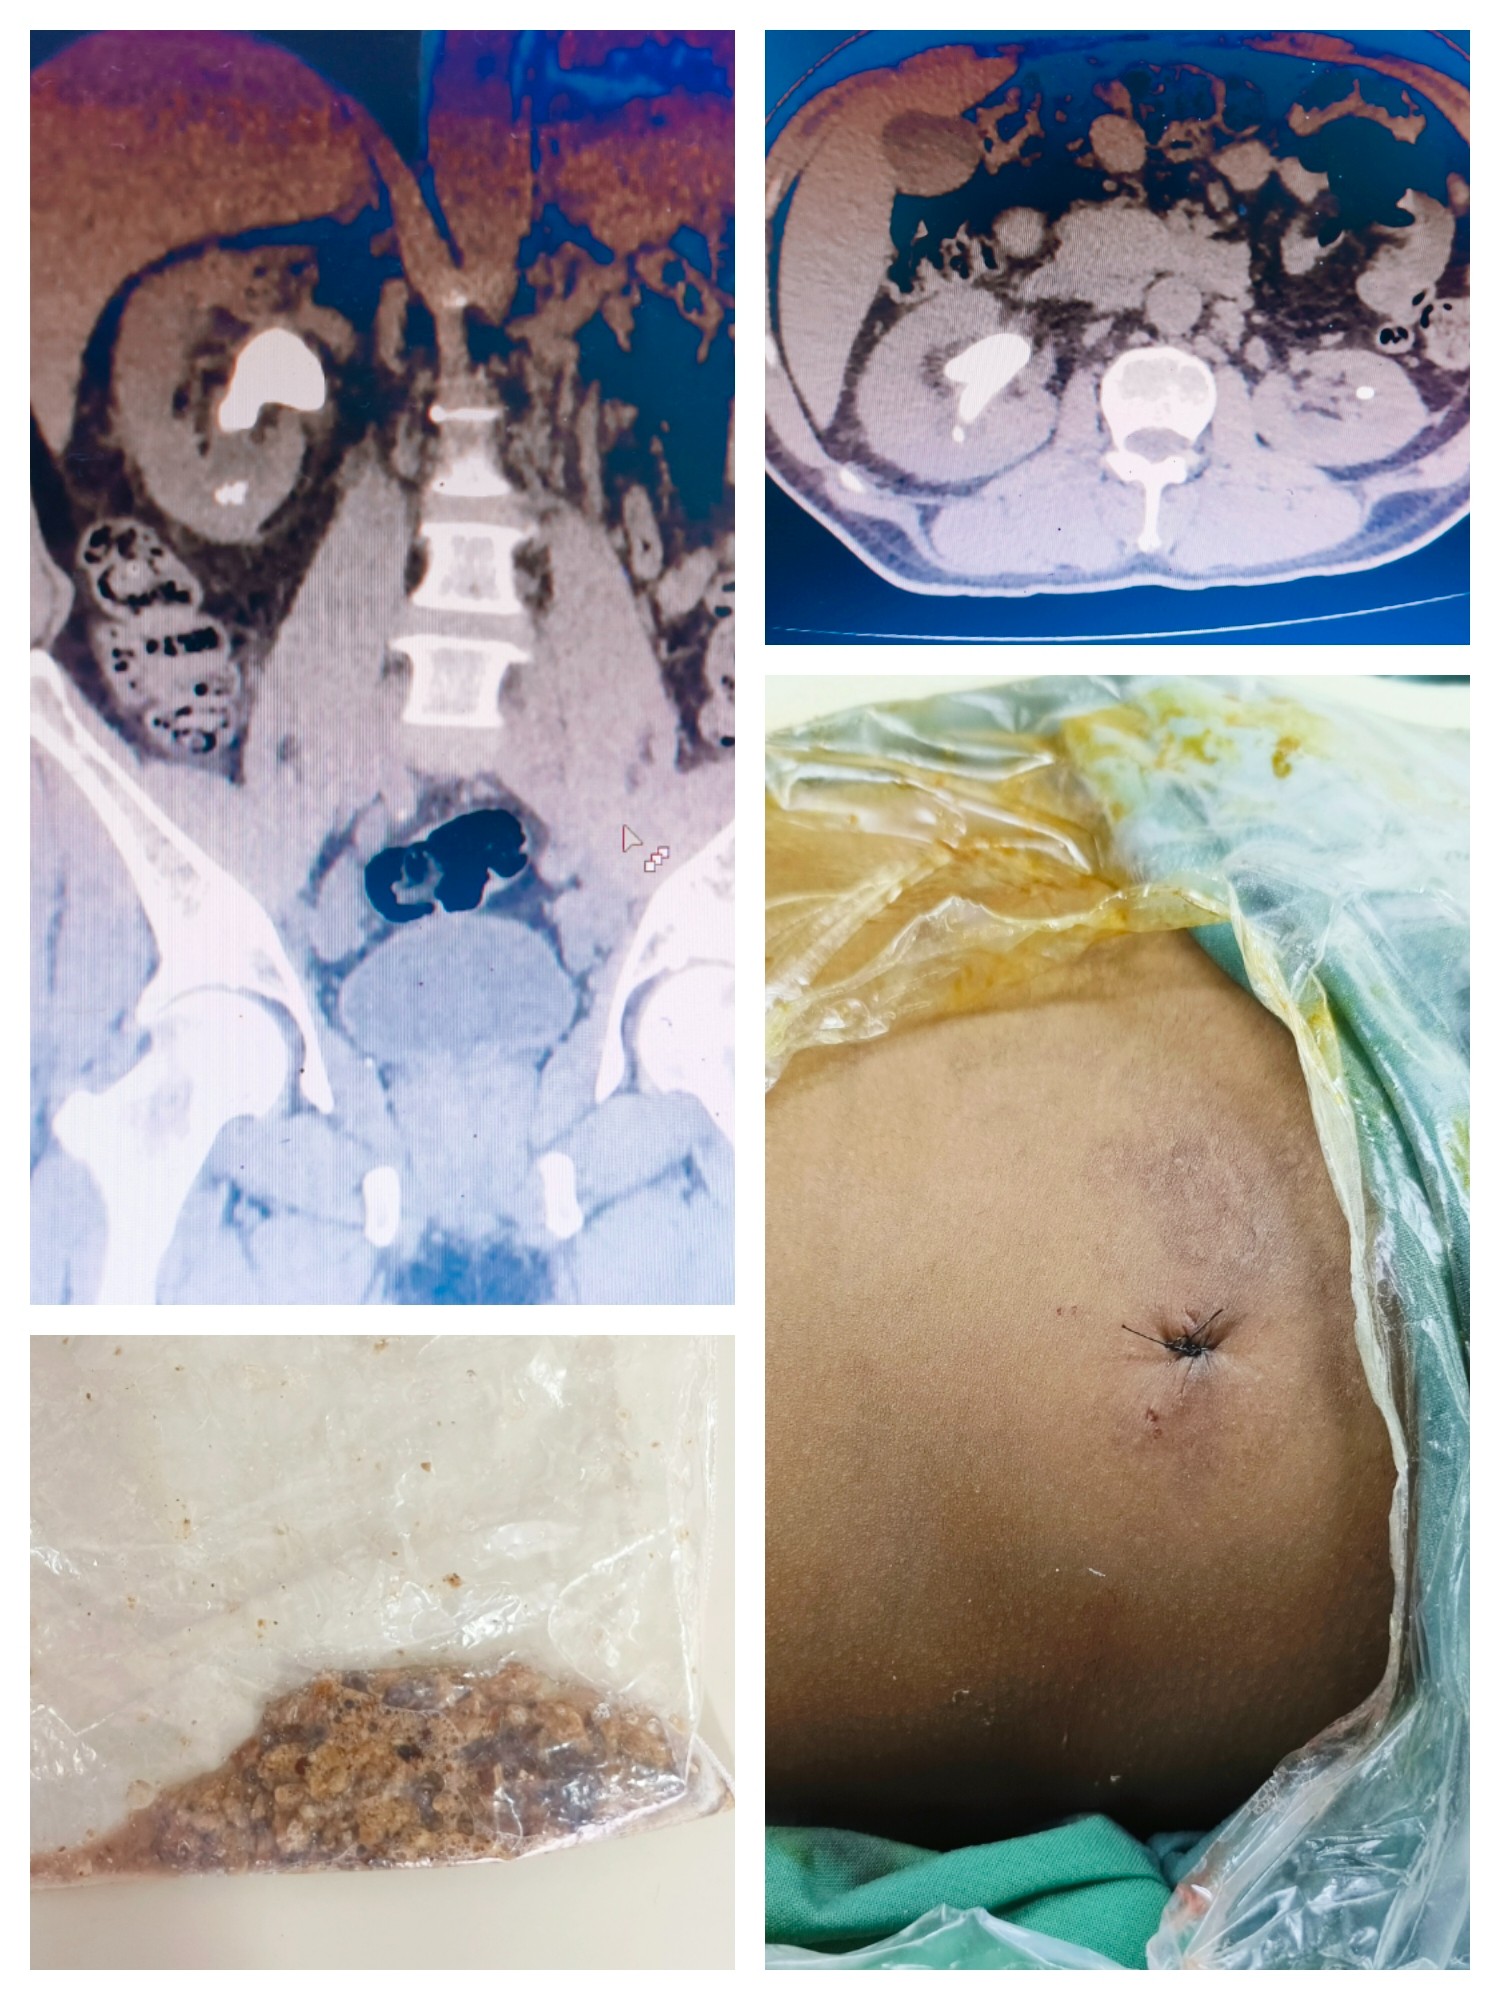

2024.2.5巴新首例PCNL手术患者CT及微创手术伤口

2月5日,冯武兵在莫港总院泌尿外科医生的配合下顺利为MoMo完成了PCNL手术,手术耗时约2小时,腰部伤口仅0.6cm,术中出血仅10ml。他使用钬激光技术将结石充分碎裂并彻底冲洗出来,术后实现伤口无管化处理,患者全程生命体征稳定,术后未出现出血、发热等手术并发症。同时,患者在住院期间也仅仅花费了100基纳就完成了在国外需要5万~10万基纳的微创手术治疗。